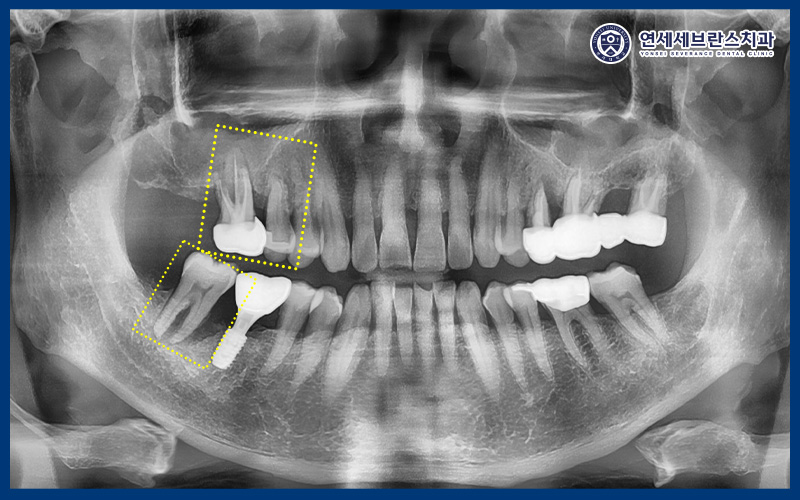

파노라마 사진을 촬영해 보니,

오른쪽 위 치아 2개와 아래 맨 뒤 치아의

잇몸뼈 소실로 치주염이 진행된 것을

확인할 수 있었습니다.

위쪽 맨 뒤 치아의 경우

동요도가 3도로 매우 심했으며,

잇몸뼈 소실이 크게 진행된 상태라

통증이 지속되고 있었습니다.